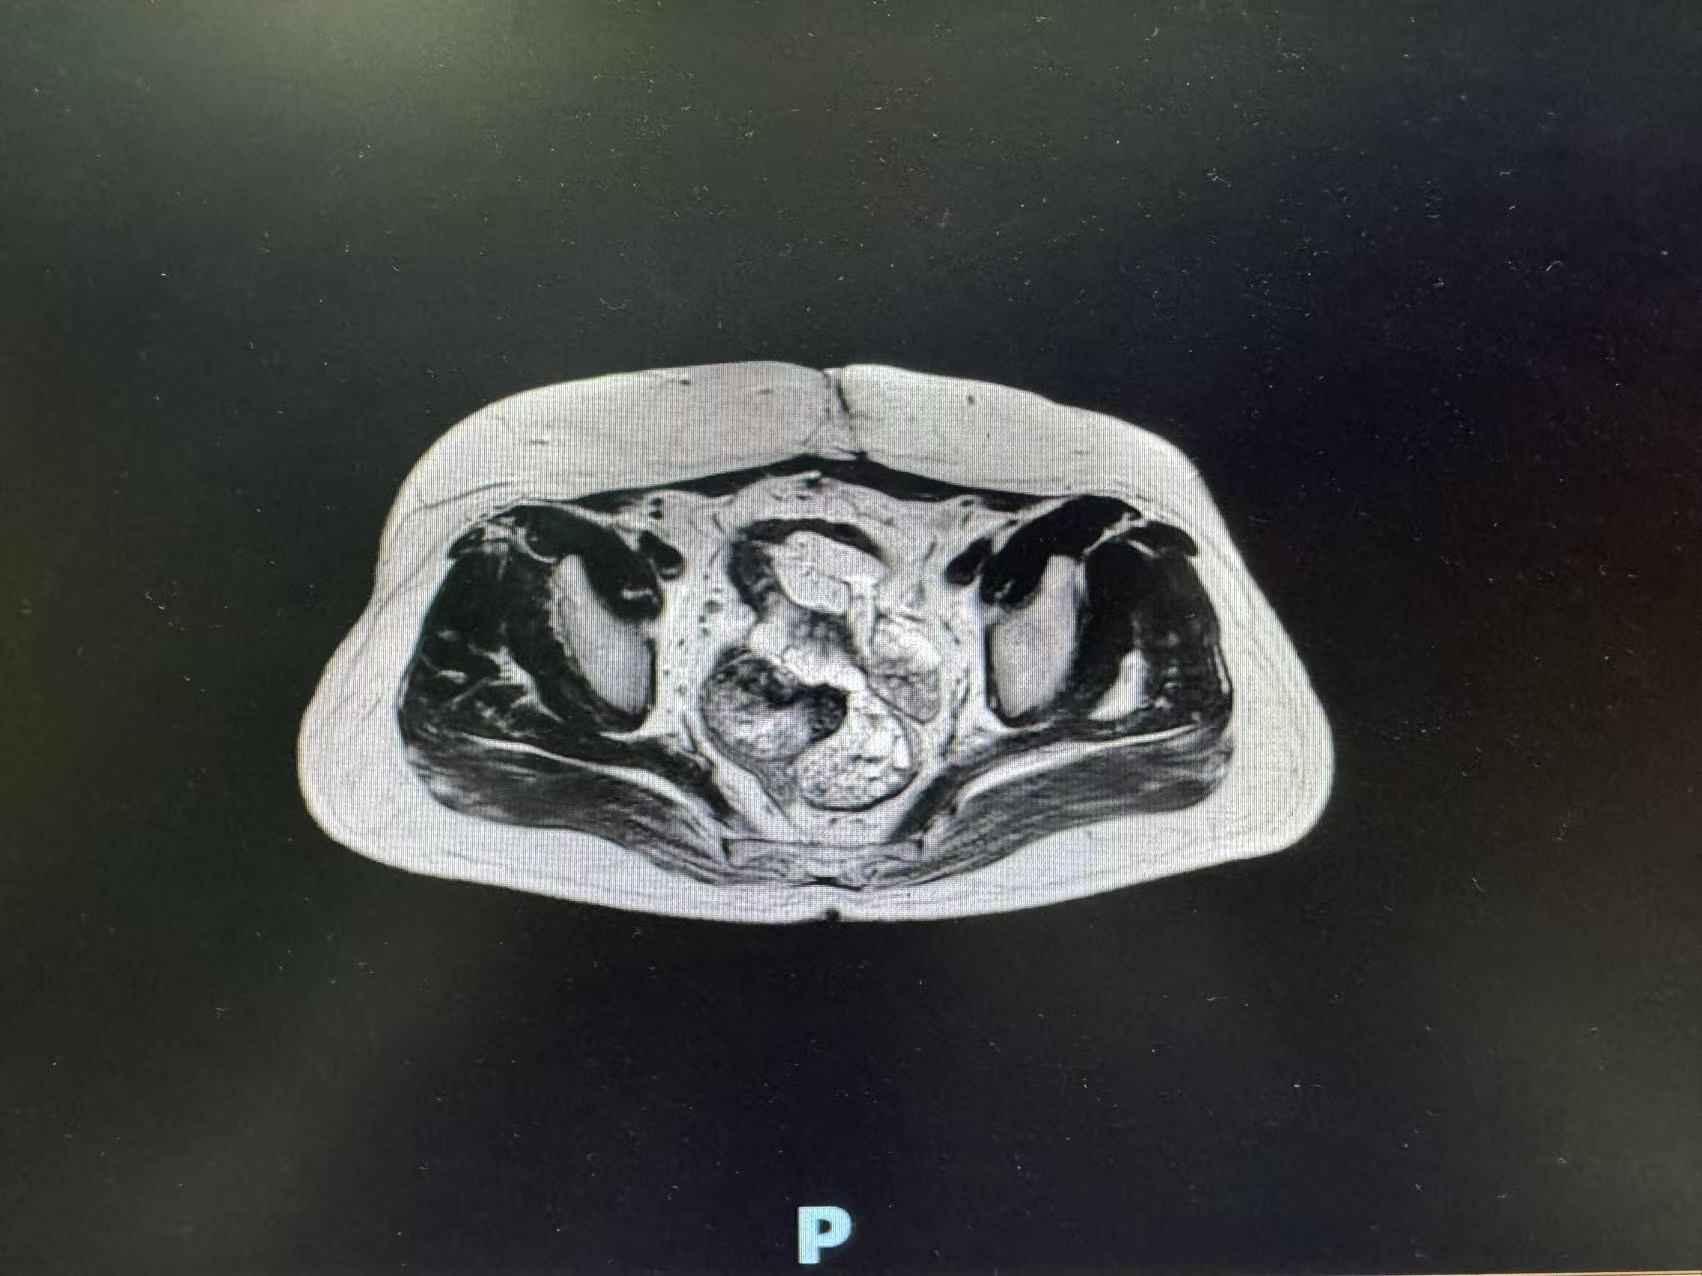

术前肿瘤影像数据

入院后,张玉宝教授立即带领团队对患者病情进行全面细致评估,启动多学科会诊(MDT),联合影像中心、麻醉科、重症医学科等专家,精准研判肿瘤侵犯范围、血管受累程度及脏器功能状态。结合二次开腹手术的特殊性,团队反复优化手术入路与切除策略,充分预判术中可能出现的致命风险,制定周密的个体化手术方案与应急预案,为手术安全筑牢坚实基础。